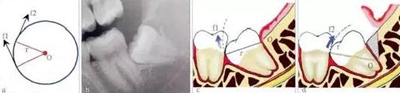

3.jpg

圖3 牙根弧形與脫位阻力。由于牙根表面弧度不同,牙槽窩的彎曲弧度也不同,導(dǎo)致同樣分牙后(綠色部分為先期去除的牙體組織),牙根脫位時阻力方向不同。左圖中牙根脫位時,發(fā)生以O(shè)為旋轉(zhuǎn)中心的圓周運動,阻力位點(f)脫位時,運動方向

為箭頭方向,可以順利脫位。而在右圖中,旋轉(zhuǎn)中心(O)和旋轉(zhuǎn)半徑(r)一樣的情況下,阻力位點(f)的脫位方向被牙槽窩阻擋,而不易脫位。

4.jpg

圖4 轉(zhuǎn)動軸心與圓弧運動。在圓周運動(旋轉(zhuǎn))中,圓周上所有點的運動方向(f1、f2)均為切線方向,與通過該點的半徑(r)相垂直(圖a)。當牙齒發(fā)生旋轉(zhuǎn)脫位時,其阻力點的運動方向會隨著轉(zhuǎn)動的軸心點的變化而變化,從而避開阻力。前傾

阻生智齒(圖b)脫位時,阻力分析如圖c所示,因阻力點位于旋轉(zhuǎn)中心(O)的下方,旋轉(zhuǎn)脫位時,其阻力點的運動方向(f1)是向前上的,被鄰牙所阻擋。如果按照圖d所示,去除遠中骨質(zhì)(灰色部分)或切割牙體(r)后,旋轉(zhuǎn)中心(O)下移,阻

力點的運動方向就改變?yōu)橄蚝笊希╢2),而得以避開鄰牙阻擋而脫位。